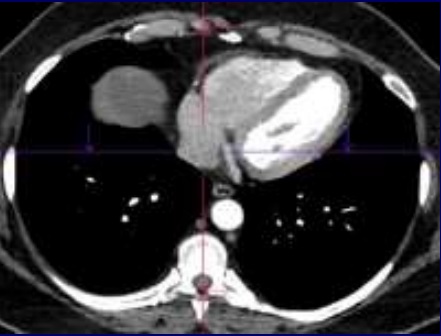

Image radiologique TDM

normale de la paroi du thorax en coupe axiale fenêtre

mediastinal . Os stenum en avant , la colonne

vertebrale en arriere et des cotes du thorax sont

très hyperdense |